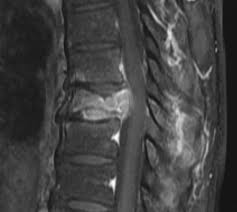

compression fracture